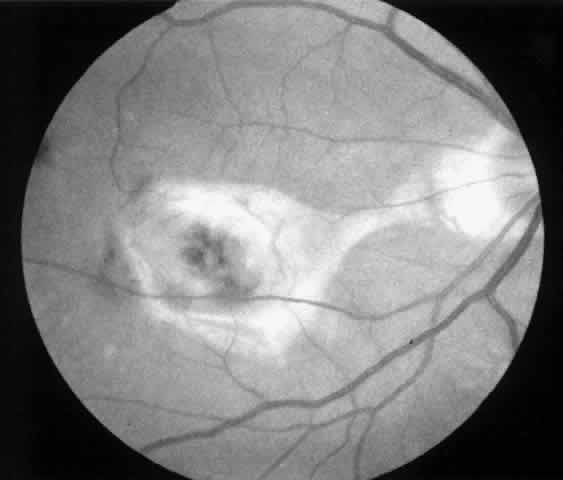

Besides being in the most advantageous location, the retinotomy should be as small as possible. Initially, we lightly diathermized the surface of the retina and then used the myringotomy blade to tease open a small hole through which an angled infusion needle was introduced.15 At the suggestion of Lambert and co-workers at Emory University, we stopped using diathermy. We now use a 120° angled, sharply pointed 36-gauge subretinal pick to pierce undiathermized neurosensory retina (Fig. 2). Occasional slight retinal hemorrhage can be controlled by transiently increasing the intraocular pressure. After the tiny hole has been made, the surgeon introduces the angled 33-gauge infusion needle beneath the retina and the assistant gently infuses balanced salt solution to elevate the neurosensory retina. This is accomplished by pushing on the plunger of a syringe that is connected to the hub of the needle by a short piece of tubing. As the fluid enters the subretinal space, attention is directed to edges of laser scars and/or adhesions to the underlying membrane (Fig. 3). Excessive infusion pressure can easily tear the retina. If areas of retina remain adherent, the infusion is stopped and the tip of an angled subretinal pick is carefully passed over the anterior surface of the membrane surface to break any residual adhesions. In a similar manner, the tip of the angled subretinal pick can be used to gently separate the thinned retina from an underlying photocoagulation scar. Occasionally, horizontal subretinal scissors are necessary to cut firm adhesions. These scissors have a similar 130° bend and blades approximately 3 mm in length to allow manipulation through an eccentric retinotomy. Trauma to foveal photoreceptors from either the pick or scissors is carefully avoided. If the retina is not mobilized over the entire photocoagulation scar, separation is achieved at least far enough into the scar to allow manipulation and extraction of the membrane without tearing the adjacent retina. The sharp tip of the angled subretinal pick is used to elevate the edge of the neovascular complex from the underlying RPE (Fig. 4). Care is taken to swing the pick in a pivoting or rotating manner to stretch or enlarge the retinotomy as little as possible. This requires close attention not only to the primary site of action at the membrane but also to the instrument shaft at the retinotomy site. In the appropriate cases, the complex dislodges easily from the underlying subfoveal RPE but remains attached to the edge of a laser scar (in recurrent cases) or to the stalk of choroidal vascular ingrowth.